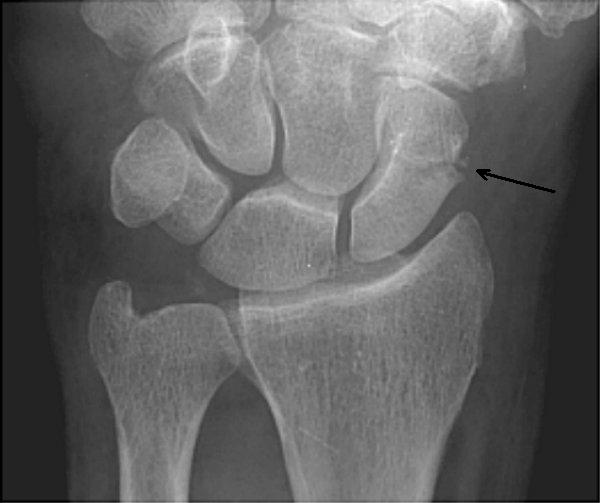

Pisiform fracture | Radiology Case | Radiopaedia.org

Pisiform fracture | Radiology Case | Radiopaedia.org from images.radiopaedia.org

Simultaneous fracture and dislocation of the pisiform has only been described twice in children 1. The pisiform bone is a sesmoid bone, or a small bone within a tendon that increases the pulley action of the muscle. For few weeks, then splint if you have no more see hand doc:

Bone fractures, commonly known as broken bones, happen to millions of people across the country each year. They are only thought to account for ~0.2% of all carpal fractures. Causes vary and treatment is dependent upon the type of fracture. 50% occur in association with other carpal fractures or distal radius fractures. Semantic scholar extracted view of isolated fracture of the pisiform bone. by b a lalanne. This disturbs the structure and strength of the bone, and leads to pain, loss of function and sometimes bleeding and injury around the site. The study of fracture of pisiform bone of wrist has been mentioned in research publications which can be found using our bioinformatics tool below. The two patients were treated with closed reduction of both the distal radius and dislocated pisiform under general anaesthesia. It is the most common carpal bone to break (fracture). The two patients were treated with closed reduction of both the distal radius and dislocated pisiform under general anaesthesia. The most common broken bones are stress fractures, rib fractures, skull fractures, hip fractures, and fractures in children. Explore more on fracture of pisiform bone of wrist below! 50% occur as isolated injuries. The pisiform bone is a sesmoid bone, or a small bone within a tendon that increases the pulley action of the muscle. Quizlet is the easiest way to study, practise and master what you're learning. Bone fractures, commonly known as broken bones, happen to millions of people across the country each year. Simultaneous fracture and dislocation of the pisiform has only been described twice in children 1.